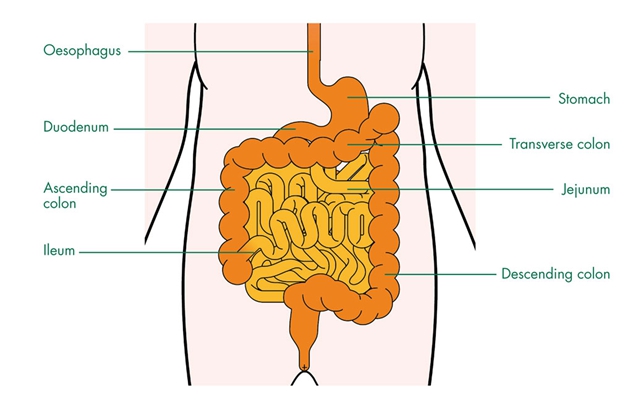

盲腸的位置 (50)

盲腸的位置 (6)

盲腸的位置 (7)

盲腸的位置 (8)

盲腸的位置 (9)

盲腸的位置 (46)

盲腸的位置 (47)

盲腸的位置 (48)

盲腸的位置 (49)

盲腸的位置 (5)

盲腸的位置 (42)

盲腸的位置 (43)

盲腸的位置 (44)

盲腸的位置 (45)

盲腸的位置 (41)

盲腸的位置 (40)

盲腸的位置 (30)

盲腸的位置 (31)

盲腸的位置 (32)

盲腸的位置 (33)